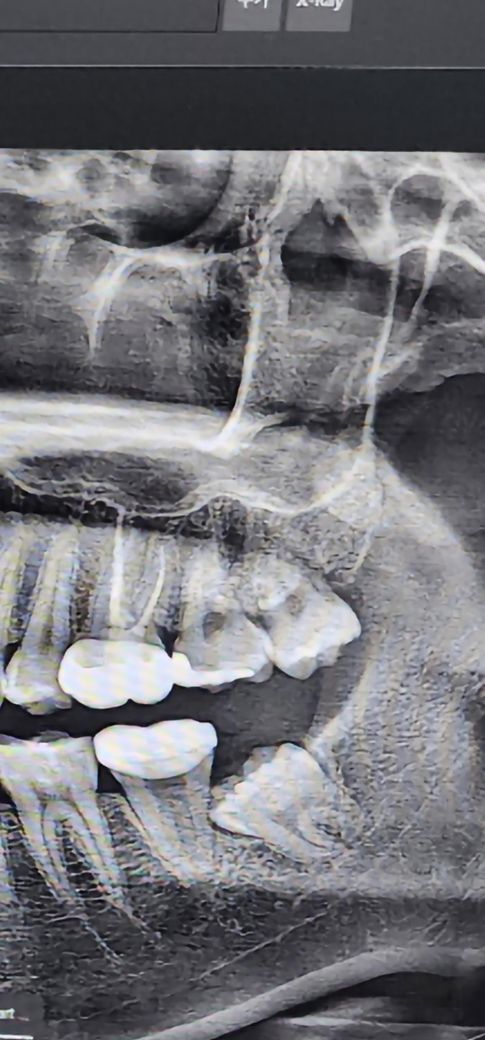

사랑니 뽑아야할 것 같은데 질문있어요

아래는 신경근처에 누워있어서 무조건 뽑아야할 것 같은데 위에는 잘 나긴 했는데 윗 잇몸에 공간이 부족하다

보니까 약간 옆으로 기울어졌고 좁아서 옆에 이빨까지

눌리는 느낌이 좀 들어서 불편한데 이거 꼭 뽑아야 할까요 뽑는거 말고 다른 방법은 없나요

• 1번 째 사진

사랑니? 사진을 봤을 경우에는 잇몸 안에 매복되어 있습니다. 또한 주변 조직의 문제를 발생시키거나 하는 것이 아니기 때문에 통증이 있거나 불편감이 없는 것이라면 굳이 발치를 할 필요가 없습니다.